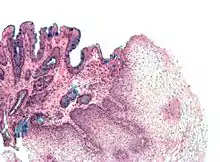

Clinical Note - Barrett's esophagitis

In Barrett's esophagitis the stratified squamous epithelium at the lower end of the esophagus is replaced by intestinal-type lining (columnar epithelium), due to reflux esophagitis. It is considered a pre-malignant condition as about 0.5% per year of patients will go on to develop esophageal cancer (adenocarcinoma of the esophagus).